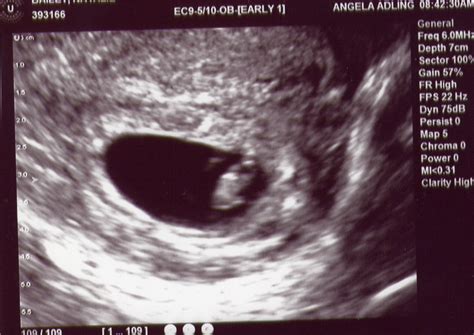

A 7 week ultrasound is a critical milestone in pregnancy, offering a wealth of information about the developing fetus. At this stage, the embryo has undergone significant growth and development, and various structures can be visualized using high-frequency ultrasound. This examination is typically performed transvaginally, providing a more detailed view of the embryo and its surroundings.

During a 7 week ultrasound, the sonographer or healthcare provider will assess several key aspects of fetal development. The embryo's size, measured from crown to rump, is usually around 10-12 millimeters in length. The heart rate can be detected, and its rhythm and frequency are evaluated to ensure they fall within normal ranges. The presence of a yolk sac, which provides nutrients to the embryo before the placenta takes over, is also confirmed. Additionally, the sonographer may identify the beginnings of limb buds, which will eventually develop into arms and legs.

- Transvaginal ultrasound provides a clearer view of the embryo and its surroundings compared to transabdominal ultrasound at this gestational age.

The detection of heart activity during a 7 week ultrasound is a significant milestone. The fetal heart begins to beat around the 6th week of gestation, and by the 7th week, its rhythm and frequency can be evaluated. A normal heart rate at this stage ranges from 100 to 180 beats per minute. Any deviations from this range may indicate potential issues, although it’s essential to consider that heart rates can vary slightly from one fetus to another.

What can be seen on a 7 week ultrasound?

+At 7 weeks, the embryo’s size, heart rate, and the presence of a yolk sac can be visualized. Limb buds may also be visible, although they are not well-defined at this stage.